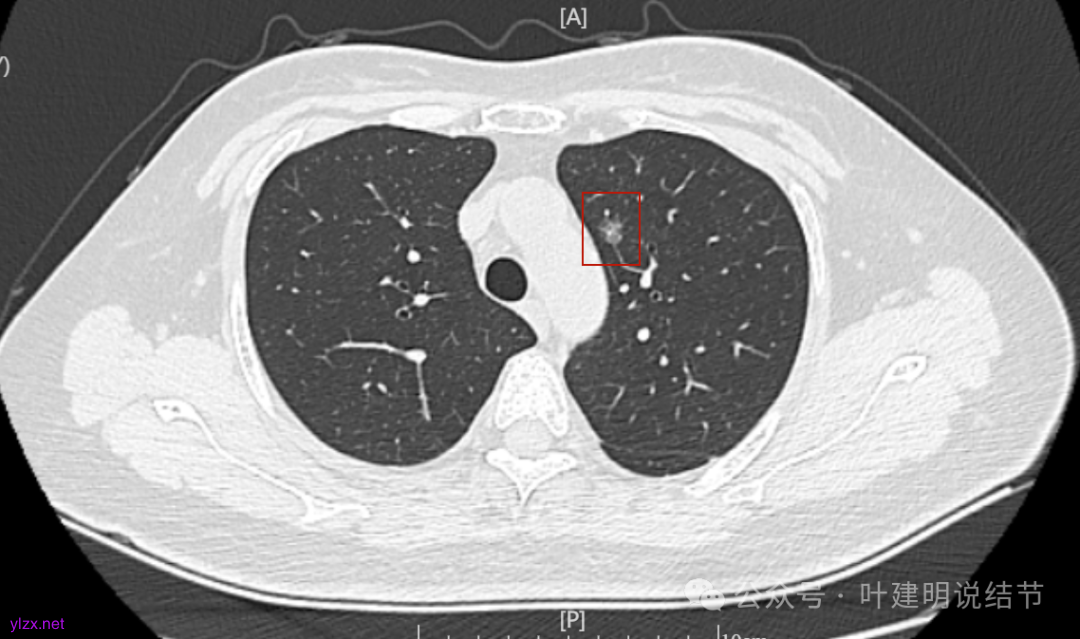

我们发现其实各病灶与三年前比说不上显著进展。

两肺多发磨玻璃结节,主病灶混合密度且有小血管进入,表面不平有毛刺,考虑微浸润性腺癌或浸润性腺癌可能性大,其余部分考虑原位癌或微浸润性腺癌,部分考虑肺泡上皮增生或不典型增生可能。总体上对比2022年说不上太明显的进展。但对于是否手术来讲,我仍倾向当年的意见,左侧的可以考虑近期亚肺叶(个人倾向楔切)切除,右侧的先随访,以后有进展并风险增加再考虑干预处理。因为要拉长两次手术的间隔,这样对机体的创伤与恢复更加有利一些。若定要仍不开刀,则建议要4-6个月复查,不过个人不太主张过于保守随访,对于像主病灶这种有少许实性成分的,不能保证肯定安全。意见供参考!